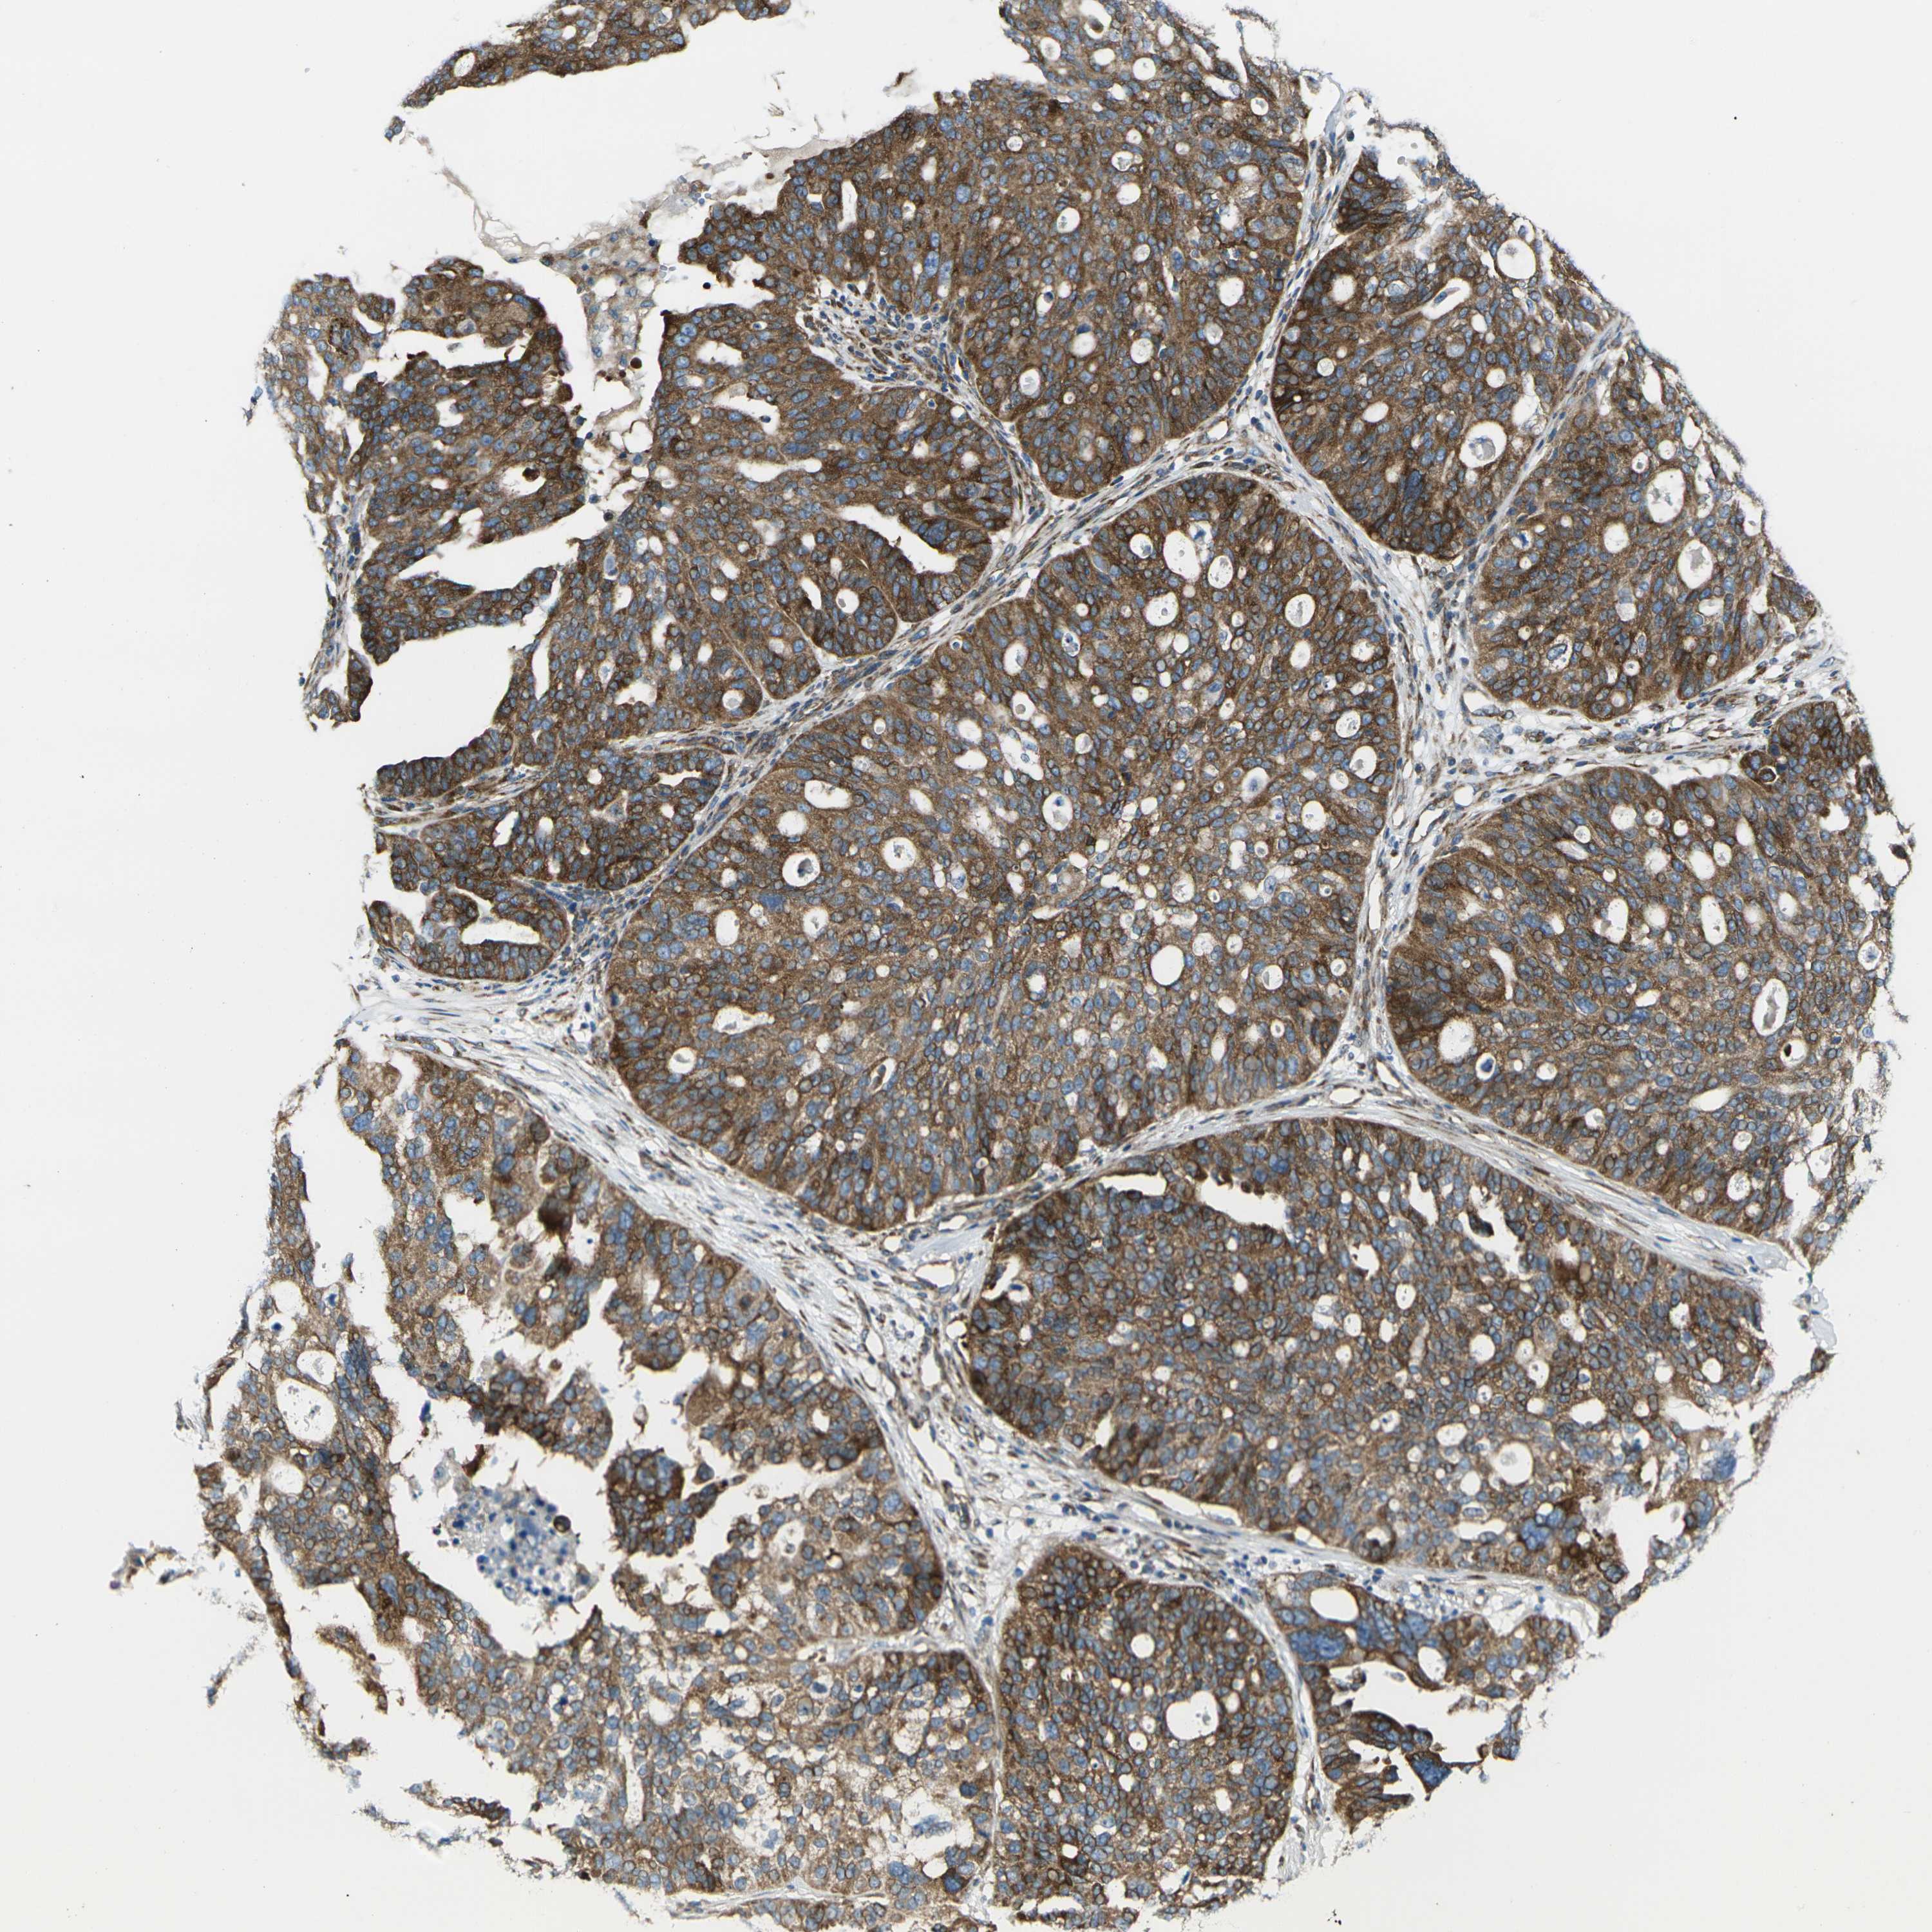

OVARIAN CANCER - Protein expressioni

A mouse-over function shows sample information and annotation data. Click on an image to view it in a full screen mode. Samples can be filtered based on level of antibody staining by selecting one or several of the following categories: high, medium, low and not detected. The assay and annotation is described here.

Note that samples used for immunohistochemistry by the Human Protein Atlas do not correspond to samples in the TCGA dataset.

Antibody stainingi

Antibody staining in the annotated cell types in the current human tissue is reported as not detected, low, medium, or high, based on conventional immunohistochemistry profiling in selected tissues. This score is based on the combination of the staining intensity and fraction of stained cells.

Each image is clickable and will lead to virtual microscopy that enables deeper exploration of all samples and also displays staining intensity scores, fraction scores and subcellular localization as well as patient and tissue information for each sample.

Antibody HPA013952

Staining

High

Medium

Low

Not detected

Intensity

Strong

Moderate

Weak

Negative

Quantity

>75%

75%-25%

<25%

None

Location

Nuclear

Cytoplasmic/membranous

Cytoplasmic/membranous,nuclear

Cystadenocarcinoma, serous, NOS

Carcinoma, endometroid

Cystadenocarcinoma, mucinous, NOS

Carcinoma, NOS